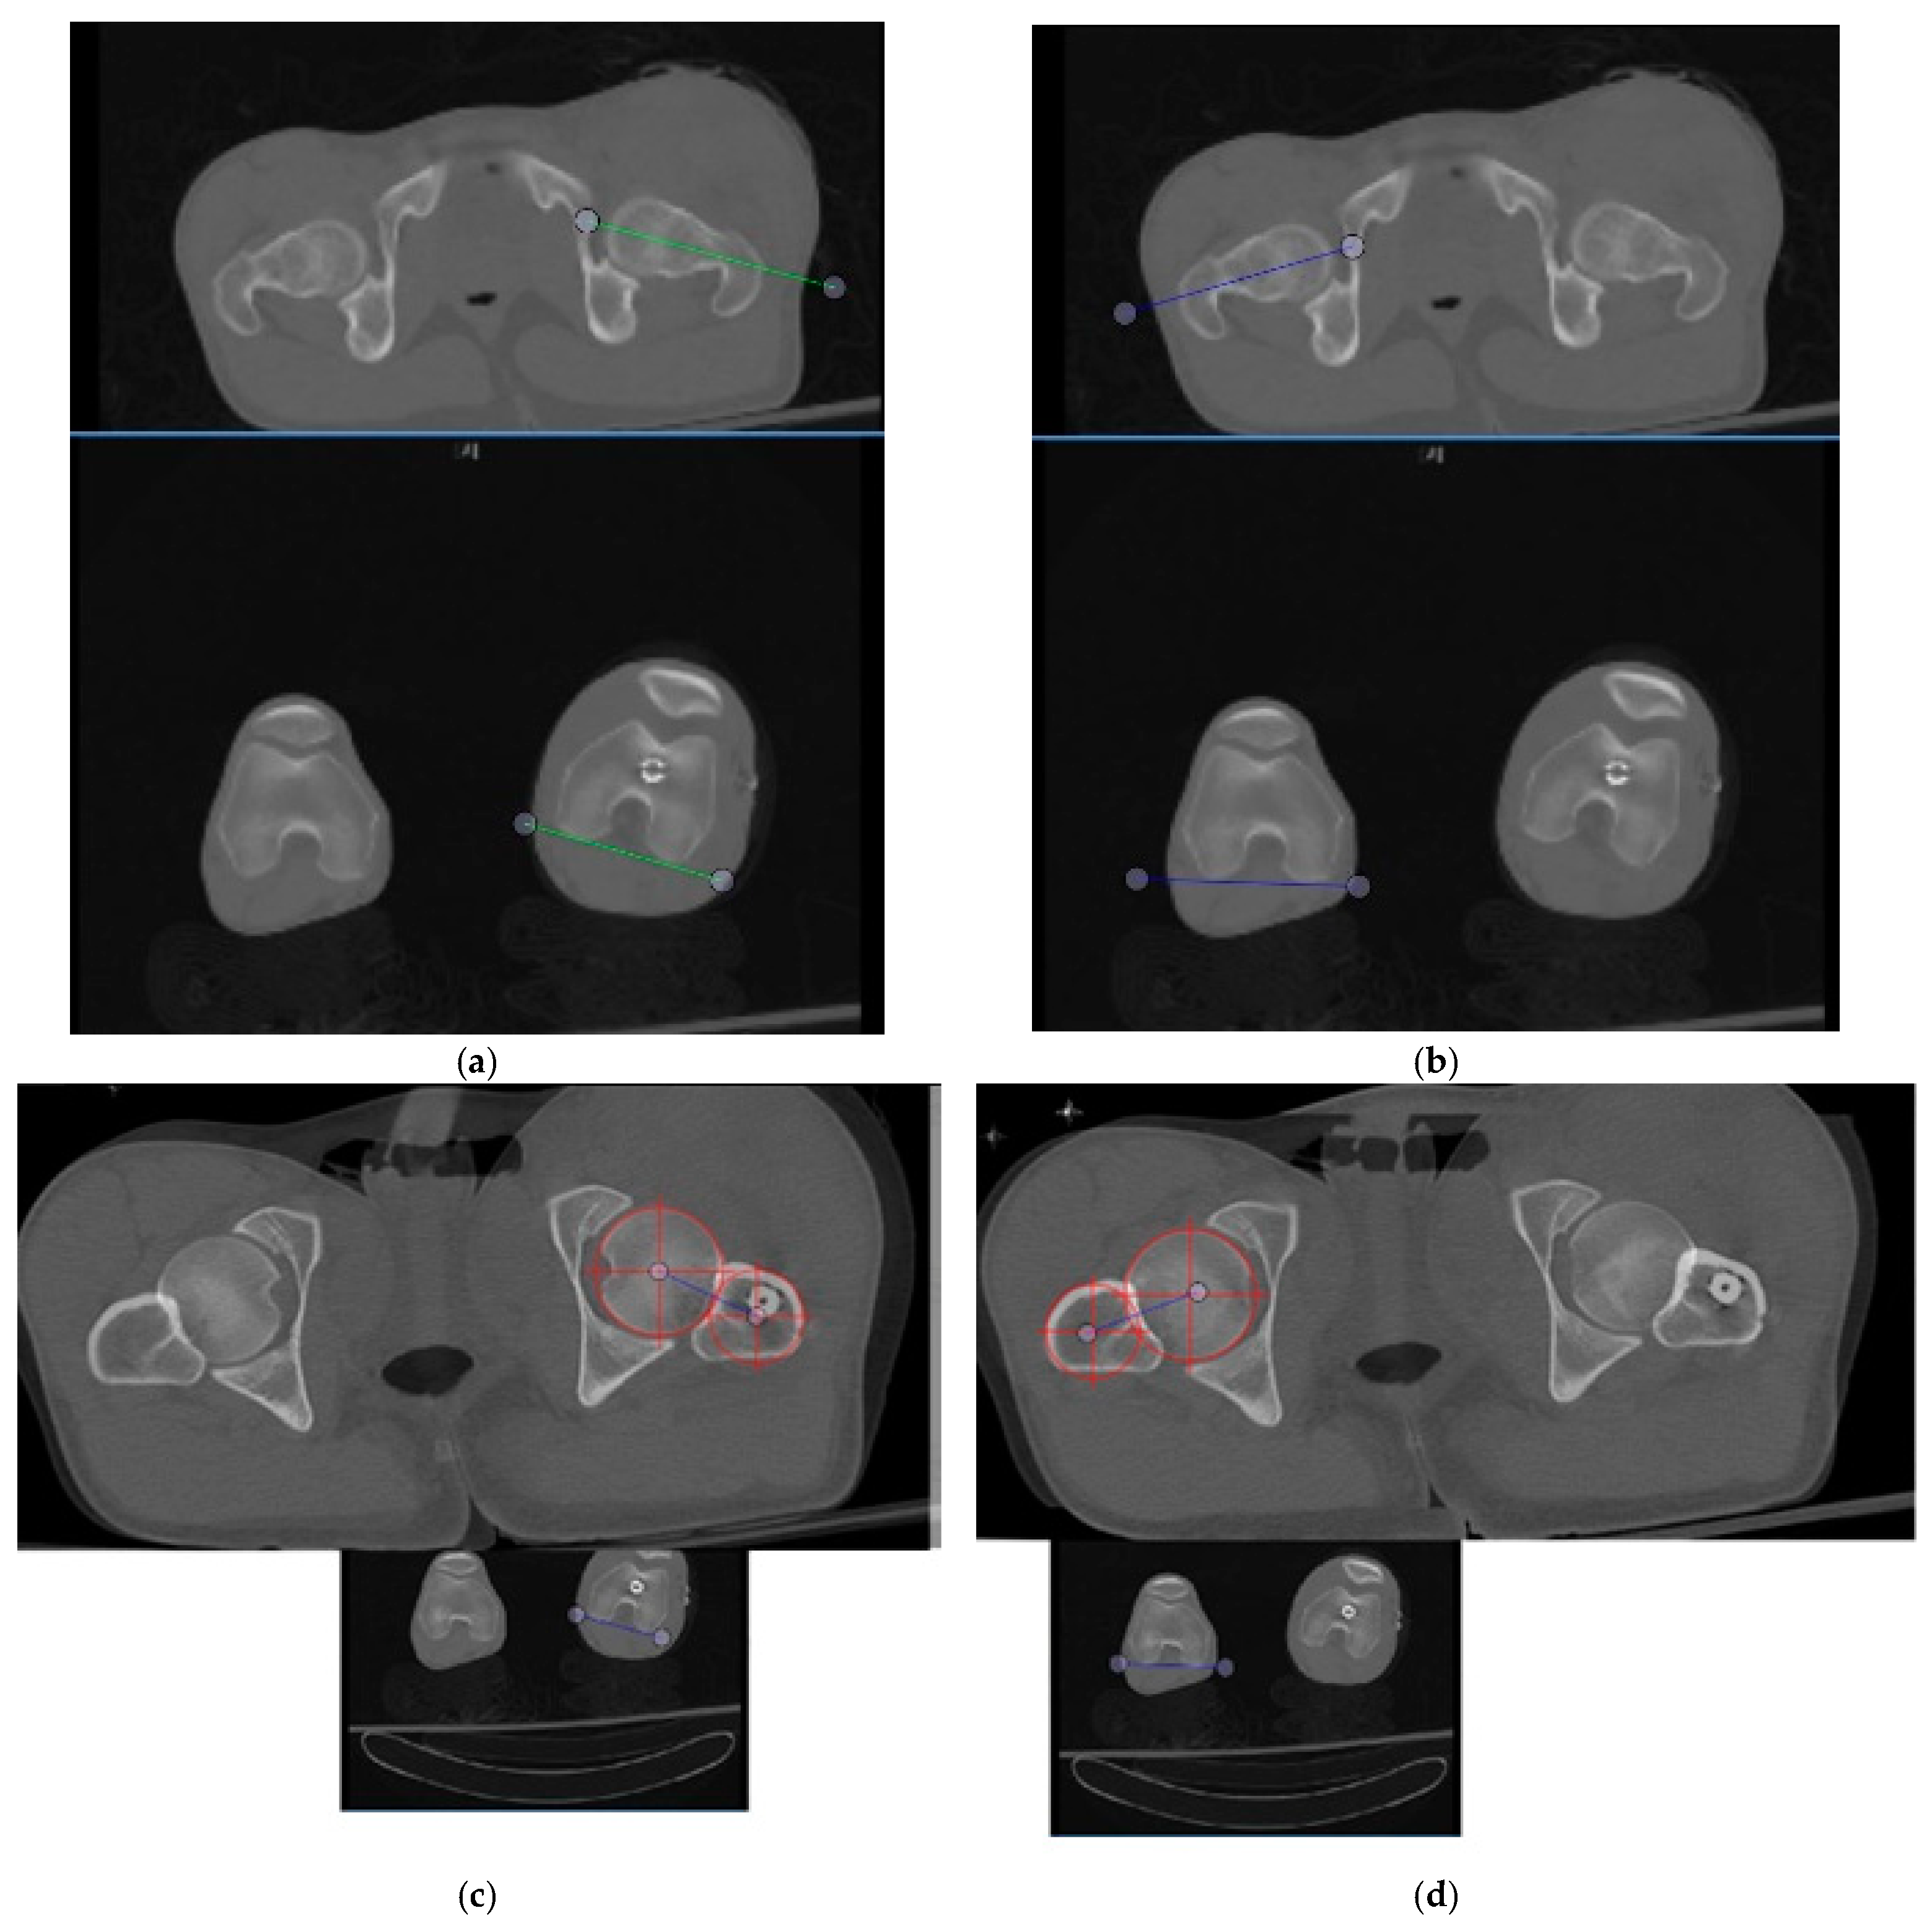

2. Materials and Methods